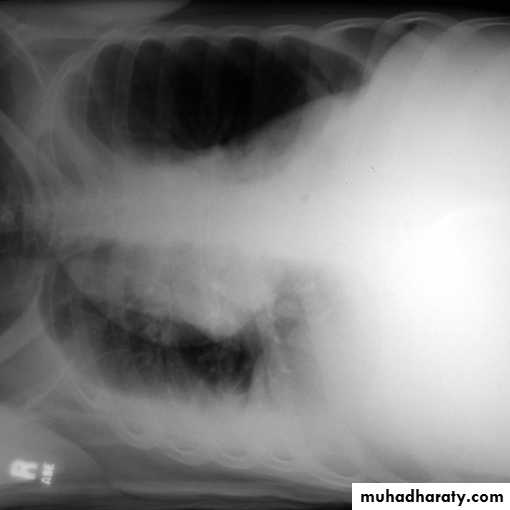

A subpulmonic effusion

(infrapulmonary effusion) accumulation of fluids between the lung & visceral pleura ..The following features are helpful :elevation of the hemidiaphragm ..right: peak of the hemidiaphragm is shifted laterally

left: increased distance between lower lobe air and gastric air bubble